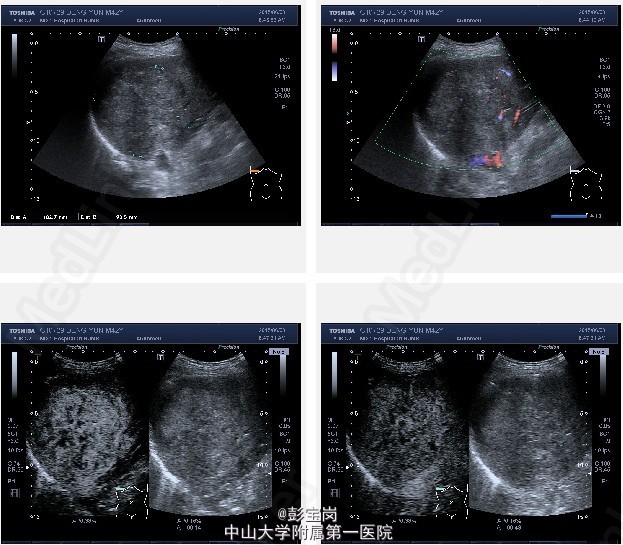

男性,42岁;因“肝癌行TACE术后,拟行手术治疗”入院。患者1月前体检发现原发性肝癌,于25天前在外院行肝动脉栓塞化疗(TACE)术。2天前患者就诊我院,查上腹CT示:右肝后叶多发结节或肿块,碘油栓塞后改变,病灶内和周边部仍有血供,门脉右后下支癌栓形成。现为进一步诊治门诊拟“肝细胞癌”收住我科。起病以来,精神食欲可,大小便通畅,体重无明显变化。既往史肾结石病史,否认肝炎病史。

查体无特殊; 检验:白细胞WBC:13.27;血红蛋白Hb:121g/L;血小板PLT:225x10^9/L;肿瘤标记物:甲胎蛋白(AFP)111.32 ug/L;癌胚抗原(CEA)9.40 ug/L;CA125 20.2 U/mL;CA19-9 11.04 U/L;HBsAg(+)

诊断:肝细胞癌 处理:右半肝切除术、胆囊切除术、腹腔粘连松解、膈肌部分切除修补、门静脉切除取癌栓、右侧肾上腺转移瘤切除